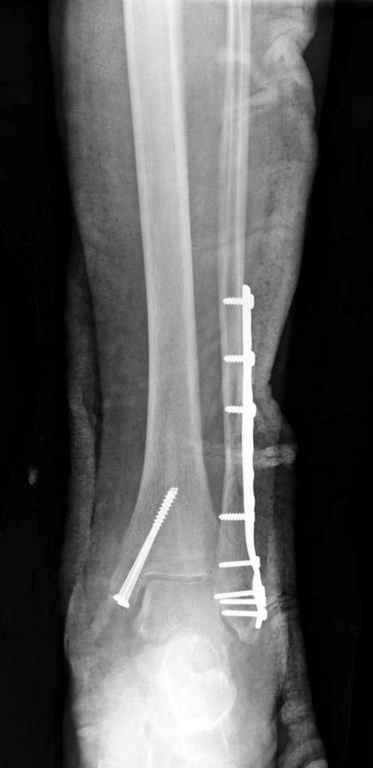

Здесь финальный снимок 73 летней с

сопутствующей шизофренией, латерально бридж

пластину (соединили дистальный конец с диафизом не трогая место перелома) и медиально перкутанно

двумя шурупами. В этам случае без гипса не

обойтись.

Как заметил, по рентгенограмме медиальная лодыжка не очень идеально репонирована. Больная кроме шизофрении страдала другими соматическими заболеваниями, и во время операции от анестезиолога получил рекомендацию поторопиться, поэтому решили закрыто, а так тенденция лечить